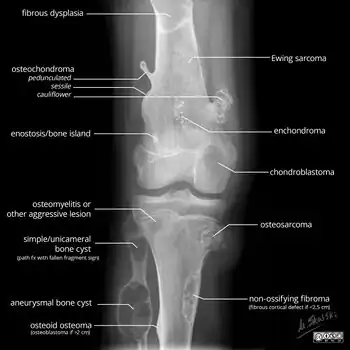

A bone tumor may be felt on examination, following which a plain X-ray is usually carried out.[4][13] Imaging is interpreted with the location of the lesion and the person's age being taken into account.[14]

X-ray appearances of different types of bone tumors in < 30 years.